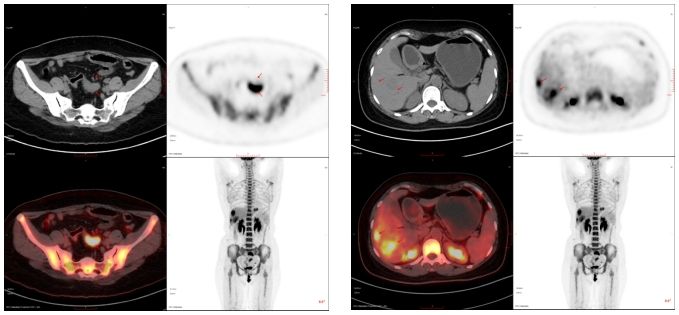

40歲,女,外院查腫瘤標(biāo)志物示:癌胚抗原(CEA)411.00 ng/ml,糖類抗原19-9(CA19-9)30.0 U/ml;來我科行PET/CT檢查。

PET/CT診斷:乙狀結(jié)腸癌伴肝臟、淋巴結(jié)多發(fā)轉(zhuǎn)移;隨后病理確診為乙狀結(jié)腸腺癌。